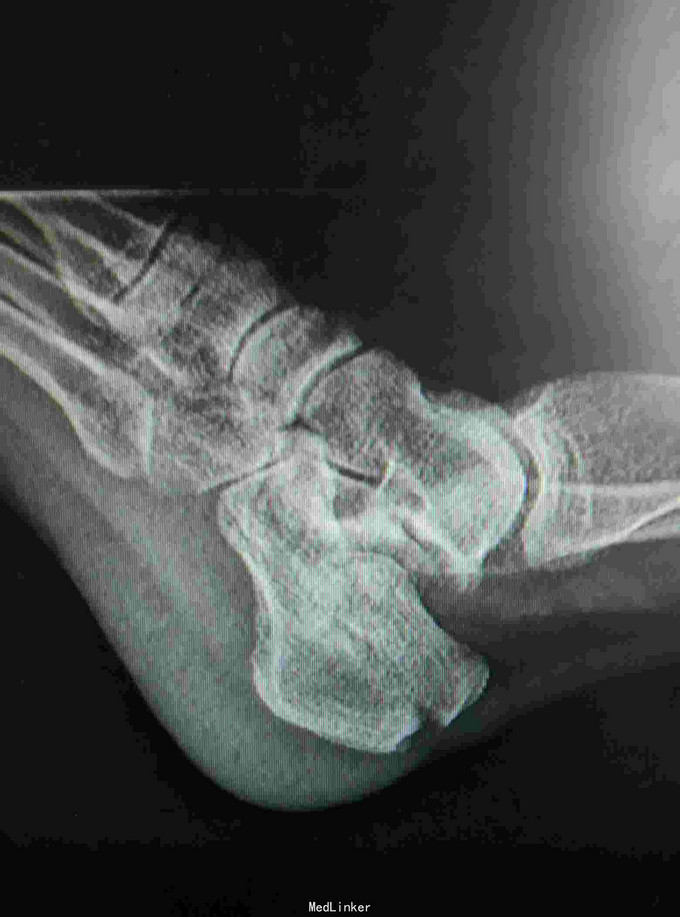

右足跟部肿痛,活动受限2小时 患者因高处坠落右足跟着地,当即出现右足跟肿痛,活动受限,余未诉特殊不适。急诊入院摄片提示跟骨骨折。

查体:脊柱生理弯曲存在,骨盆挤压分离实验阴性,双上肢肌力、活动正常,左下肢肌力、活动正常,右膝活动无明显异常,右足跟肿胀明显,无张力性水泡,皮下淤青,右踝关节活动稍受限。 辅查:平片及CT提示右跟骨粉碎性骨折

诊断:右跟骨粉碎性骨折 治疗:骨折切开复位内固定